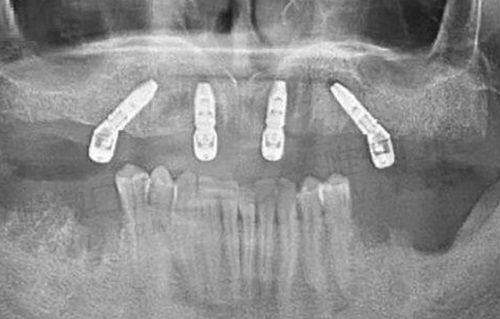

黎洪强简介: 黎洪强,目前担任中山市好民生口腔门诊部的主治医师,拥有超过十年的牙科诊疗经验。他在口腔医疗领域积累了丰富的专業知识,尤其擅长微创种植、即刻拔牙种植、上颌窦提升及骨移植等技术。作为疑难种植的医生,黎洪强医生拥有美国罗马琳达大学的种植专業硕士学位,并曾多次前往美国、德国、韩国等很多国家的先进牙科学院进行深造。他还应邀参与各类种植体公司的学术研讨会,并担任AB种植体的特邀讲师。黎医生在前牙个性化美学修复及全口种植修复方面也具有深厚的造诣。

黎洪强擅长项目: 微创种植、卽刻拔牙种植、上颌窦提升、骨移植

黎洪强医生在卽刻拔牙种植领域具有杰出的专業技能,深受患者的赞誉。他的娴熟技术和细致入微的服务,使得许多患者在接受治疗后都感到满意,纷纷给予了高度评价。